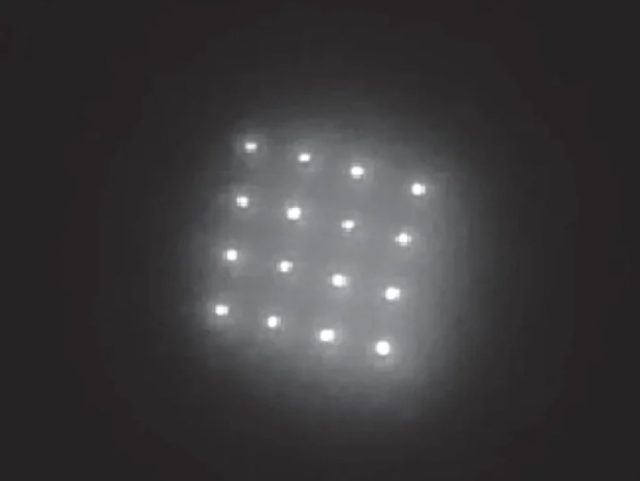

Die Forscher haben dazu einen neuen Farbstoff entwickelt, der aus Nanokristallen, sogenannten Quantenpunkten, besteht. Der kann mindestens fünf Jahre lang unter der Haut verbleiben und sendet Nahinfrarotlicht aus, das von einem speziell ausgerüsteten Smartphone ausgelesen werden kann.

Dieser neuer Farbstoff besteht aus Nanokristallen, sogenannten Quantenpunkten. Das Tattoo kann mindestens fünf Jahre lang unter der Haut verbleiben, wobei es als Signal das Nah-Infrarot-Licht aussendet.

Zur Erstellung dieser quasi „Online-Patienten“ Krankenakte entwickelten die Forscher einen neuen Typ von Quantenpunkten auf Kupferbasis, die Licht im nahen Infrarot-Spektrum abstrahlen.

Die Punkte sind nur etwa 4 Nanometer im Durchmesser groß, aber sie sind in biokompatible Mikropartikel eingekapselt, die Kugeln mit einem Durchmesser von etwa 20 Mikrometern bilden. Diese Verkapselung ermöglicht es, dass der Farbstoff, nachdem er zusammen mit einem Impfstoff injiziert wurde, unter der Haut verborgen bleibt.(Wie Bill Gates die EU übernimmt: ID2020, ein EU-weites Vermögensregister und Breakthrough Energy)

„Durch die gemeinsame Verabreichung eines Impfstoffs könnte das Partikelmuster in der Haut als Impfpass vor Ort dienen.“

Wenn das Pflaster auf die Haut aufgeklebt wird, lösen sich die 1,5 Millimeter langen Mikronadeln teilweise auf und geben ihre Nutzlast innerhalb von etwa zwei Minuten ab. Die kleinen Mikrokristalle lösen sich nicht auf, sondern verbleiben an der Stelle, wie QR-Punkte und können ausgelesen werden. Hier eine Darstellung aus dem Bericht des MIT: